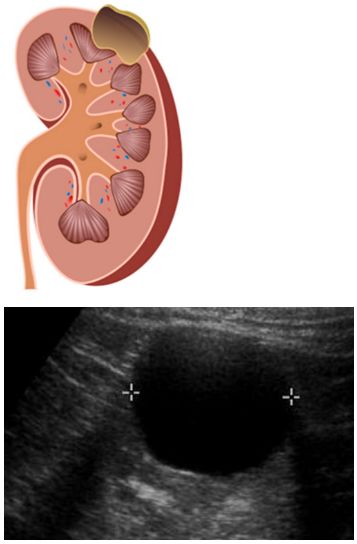

신장 낭종이 작고 증상이 없는 경우에 일반적으로 별도의 치료 없이 정기적인 영상검사(초음파, CT 등)를 통해 크기 변화나 낭종 내부의 상태를 관찰하는 방식이 가장 먼저 선택됩니다. 단순 낭종은 시간이 지나도 크게 변화하지 않는 경우가 많아 특별한 조치가 필요하지 않습니다.

증상을 유발하는 신장 낭종에 대해 비교적 간단한 시술로는 낭종 천자가 있습니다. 피부를 통해 바늘을 삽입하여 낭종 내부에 고여 있는 액체를 흡입하는 방식입니다. 초음파나 CT의 영상 유도하에 시술이 이루어지며, 낭종 크기를 줄여 통증이나 압박 증상을 완화시킬 수 있습니다.